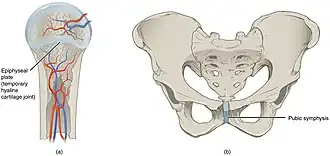

Primary cartilaginous joints are known as "synchondrosis". These bones are connected by hyaline cartilage and sometimes occur between ossification centers. This cartilage may ossify with age.

Some examples of primary cartilaginous joints in humans are the "growth plates" between ossification centers in long bones. These joints allow very little movement, such as in the spine or ribs.

Secondary cartilaginous joints are known as "symphysis". These include fibrocartilaginous and hyaline joints, which usually occur at the midline. Some examples of secondary cartilaginous joints in human anatomy would be the manubriosternal joint (between the manubrium and the body of the sternum), intervertebral discs, and the pubic symphysis. Articulating bones at a symphysis are covered with hyaline cartilage and have a thick, fairly compressible pad of fibrocartilage between them. Cartilaginous joints allow little movement, as summarized above.

The gap separating the bones at a symphysis may be narrow or wide. Examples in which the gap between the bones is narrow include the pubic symphysis and the manubriosternal joint. At the pubic symphysis, the pubic portions of the right and left hip bones of the pelvis are joined together by fibrocartilage across a narrow gap. Similarly, at the manubriosternal joint, fibrocartilage unites the manubrium and body portions of the sternum.